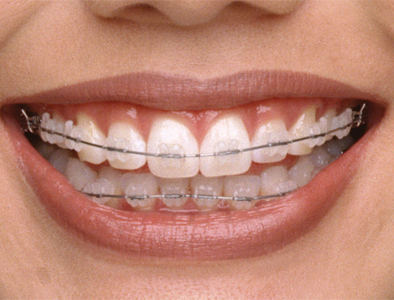

廊坊圣洁口腔医院陶瓷托槽矫治

廊坊圣洁口腔医院的专家说,陶瓷托槽矫治与普通的金属托槽相比较为显著的特性就是美观。无色、透明的托槽很好地实现了矫治过程的隐蔽性,其良好的生物相容性也避免了因长时间使用属托槽引起的牙面发暗、牙龈发炎、口腔溃疡等不良反应,更利于口腔健康。》》》相关阅读:廊坊市民龅牙会有哪些危害

1、美观,不易察觉,配合透明结扎圈使用更加美观舒适。

5、矫治器表面光滑,圆顿,不刺激牙龈,对唇颊组织摩擦力小,不刺激,感觉舒适。

7、不影响发音,不影响咀嚼食物,能对各种畸形进行矫治,且矫治效果良好。陶瓷固定矫治器即是矫治器的托槽为陶瓷,其无色透明,美观,可使您在治疗过程中始终保持自信的微笑。

廊坊圣洁口腔医院的专家说,陶瓷托槽矫治适合牙列不齐、牙齿畸形比较严重等,尤其适用于对美观要求较高的人群。托槽具有良好的抗污染性和抗变色能力,只要患者朋友注意口腔卫生,就可以使托槽一直保持透明状态。由于氧化铝陶瓷具有超高的硬度,为不锈钢的九倍,因而不会变形,具有很好的尺寸稳定性。陶瓷托槽基底与粘结剂之间为化学结合,受力均匀,不易脱落,明显减少复诊次数。